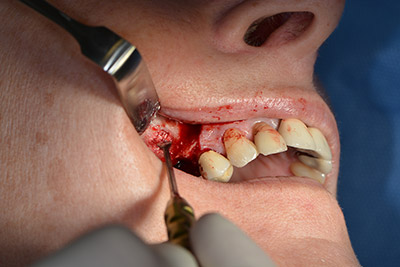

Die anschließenden Bohrungen werden mit einer reduzierten Umdrehungszahl von 300/min durchgeführt. Hier zeigt sich einer der Vorteile der Implantmed. Das chirurgische Protokoll kann voreingestellt werden – die einzelnen Positionen sind über einen einfachen Druck auf die Position „P“ der Fußsteuerung anwählbar. (Abb. 10 bis 11)

Die nächste programmierte Position ist bereits die Implantateinbringung und in unserem Hause mit einer Kraft von 32 Ncm voreingestellt (Abb. 12).